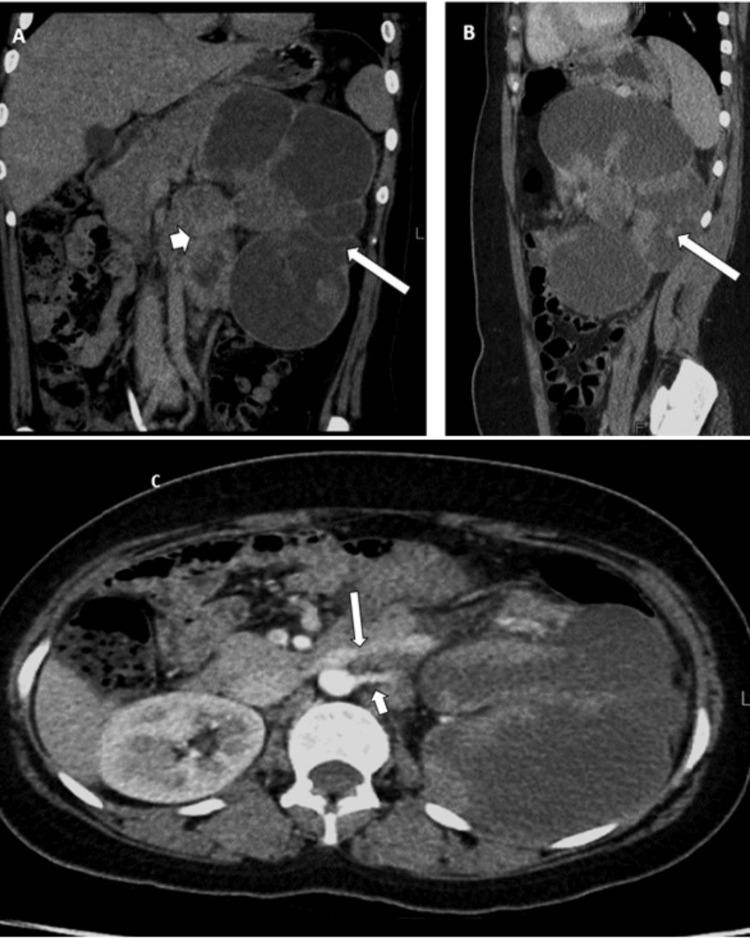

Xp11.2 translocation renal cell carcinoma (Xp11.2 RCC) is a rare tumor, occurring more frequently in childhood than in adulthood. It results from Xp11.2 chromosome translocations and the fusion of the transcription factor E3 (TFE3) gene. In this context, we present a case report of an 18-year-old female who was diagnosed with Xp11.2 RCC following open radical nephrectomy and lymph node dissection on the left side. The histopathological analysis indicated stage T3aN1Mx disease, which was confirmed through immunohistochemistry (IHC) and fluorescent in situ hybridization (FISH). The patient remained under observation until March 2023 when systemic scans uncovered the presence of ascites, peritoneal carcinomatosis, and left supraclavicular lymphadenopathy. A subsequent biopsy reaffirmed the primary disease, leading to the planning of systemic treatment involving tyrosine kinase inhibitors (TKIs) and immunotherapy. However, due to financial constraints, the patient's treatment options were limited to sunitinib initially. The current plan involves reevaluation after three months using scans to determine the subsequent course of treatment. Our case report offers crucial insights into the clinical presentation, diagnosis, and treatment of this rare malignancy. This enhances medical understanding, guides research, and improves the management of similar cases. Case reports like this share practical experiences, shaping future studies and patient care.

Xp11.2易位性肾细胞癌(Xp11.2 RCC)是一种罕见肿瘤,在儿童期比成人期更常见。它由Xp11.2染色体易位以及转录因子E3(TFE3)基因融合所致。在此背景下,我们报告一例18岁女性病例,该患者在接受左侧开放性根治性肾切除术及淋巴结清扫术后被诊断为Xp11.2 RCC。组织病理学分析显示为T3aN1Mx期疾病,通过免疫组织化学(IHC)和荧光原位杂交(FISH)得以证实。该患者一直接受观察,直至2023年3月全身扫描发现存在腹水、腹膜转移癌和左侧锁骨上淋巴结肿大。随后的活检再次确认了原发性疾病,从而制定了涉及酪氨酸激酶抑制剂(TKIs)和免疫治疗的全身治疗方案。然而,由于经济限制,患者最初的治疗选择仅限于舒尼替尼。目前的计划是三个月后通过扫描重新评估,以确定后续治疗方案。我们的病例报告为这种罕见恶性肿瘤的临床表现、诊断和治疗提供了关键见解。这增进了医学认识,指导了研究,并改善了类似病例的管理。这样的病例报告分享了实际经验,塑造了未来的研究和患者护理。